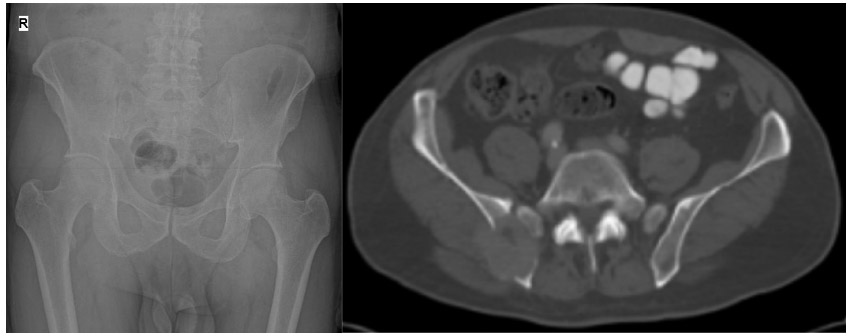

Before the surgery: X-ray and CT scans show bone destruction in the posterior part of the right pelvic bone and tumor tissue extending beyond the bone.